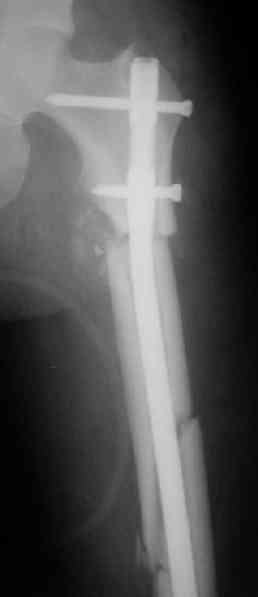

Судя по уровню перелома, винты в шейку избыточны, подойдет и диафизарный гвоздь. Все, что нужно, это тиски и труба. Загнуть сразу ниже отверстий градусов на 8-10, и вся недолга. Последние годы у нас это рутинная практика. Предызогнутые еще с завода гвозди неудобны тем, что они уже правый-левый.

Согласен, что закрытый реостеосинтез с рассверливанием и коррекцией оси - это то, что надо. Мы бы ввели в центральный отломок статических 2-3 винта, и один динамический винт в дистальном отломке.

Вот несколько. С тисками и трубой на днях сделаем.

Саша, последний штифт, пожалуй, перегнули?

Там заход сделан как для прямого штифта, не через вертел.